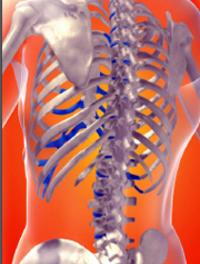

Prévention de la morbidité osseuse au cours des métastases ostéolytiques

Toutes les tumeurs primitives peuvent en théorie être responsables de métastases osseuses. Cependant, on distingue des tumeurs primitives particulièrement ostéophiles. Ainsi, l’incidence des métastases osseuses dans le cancer du sein et de la prostate est la plus forte, avec respectivement 73 % et 66 %. Les cancers de la thyroïde (42 %), du rein (35 %) et du poumon (36 %) sont également fréquemment responsables de métastases osseuses. Les tumeurs digestives ne donnent [...]